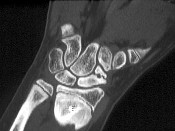

- 单项选择题根据所提供图像,最可能的诊断是 ( )

A、骨折

B、舟骨不连

C、骨髓炎

D、骨转移

E、以上都不是